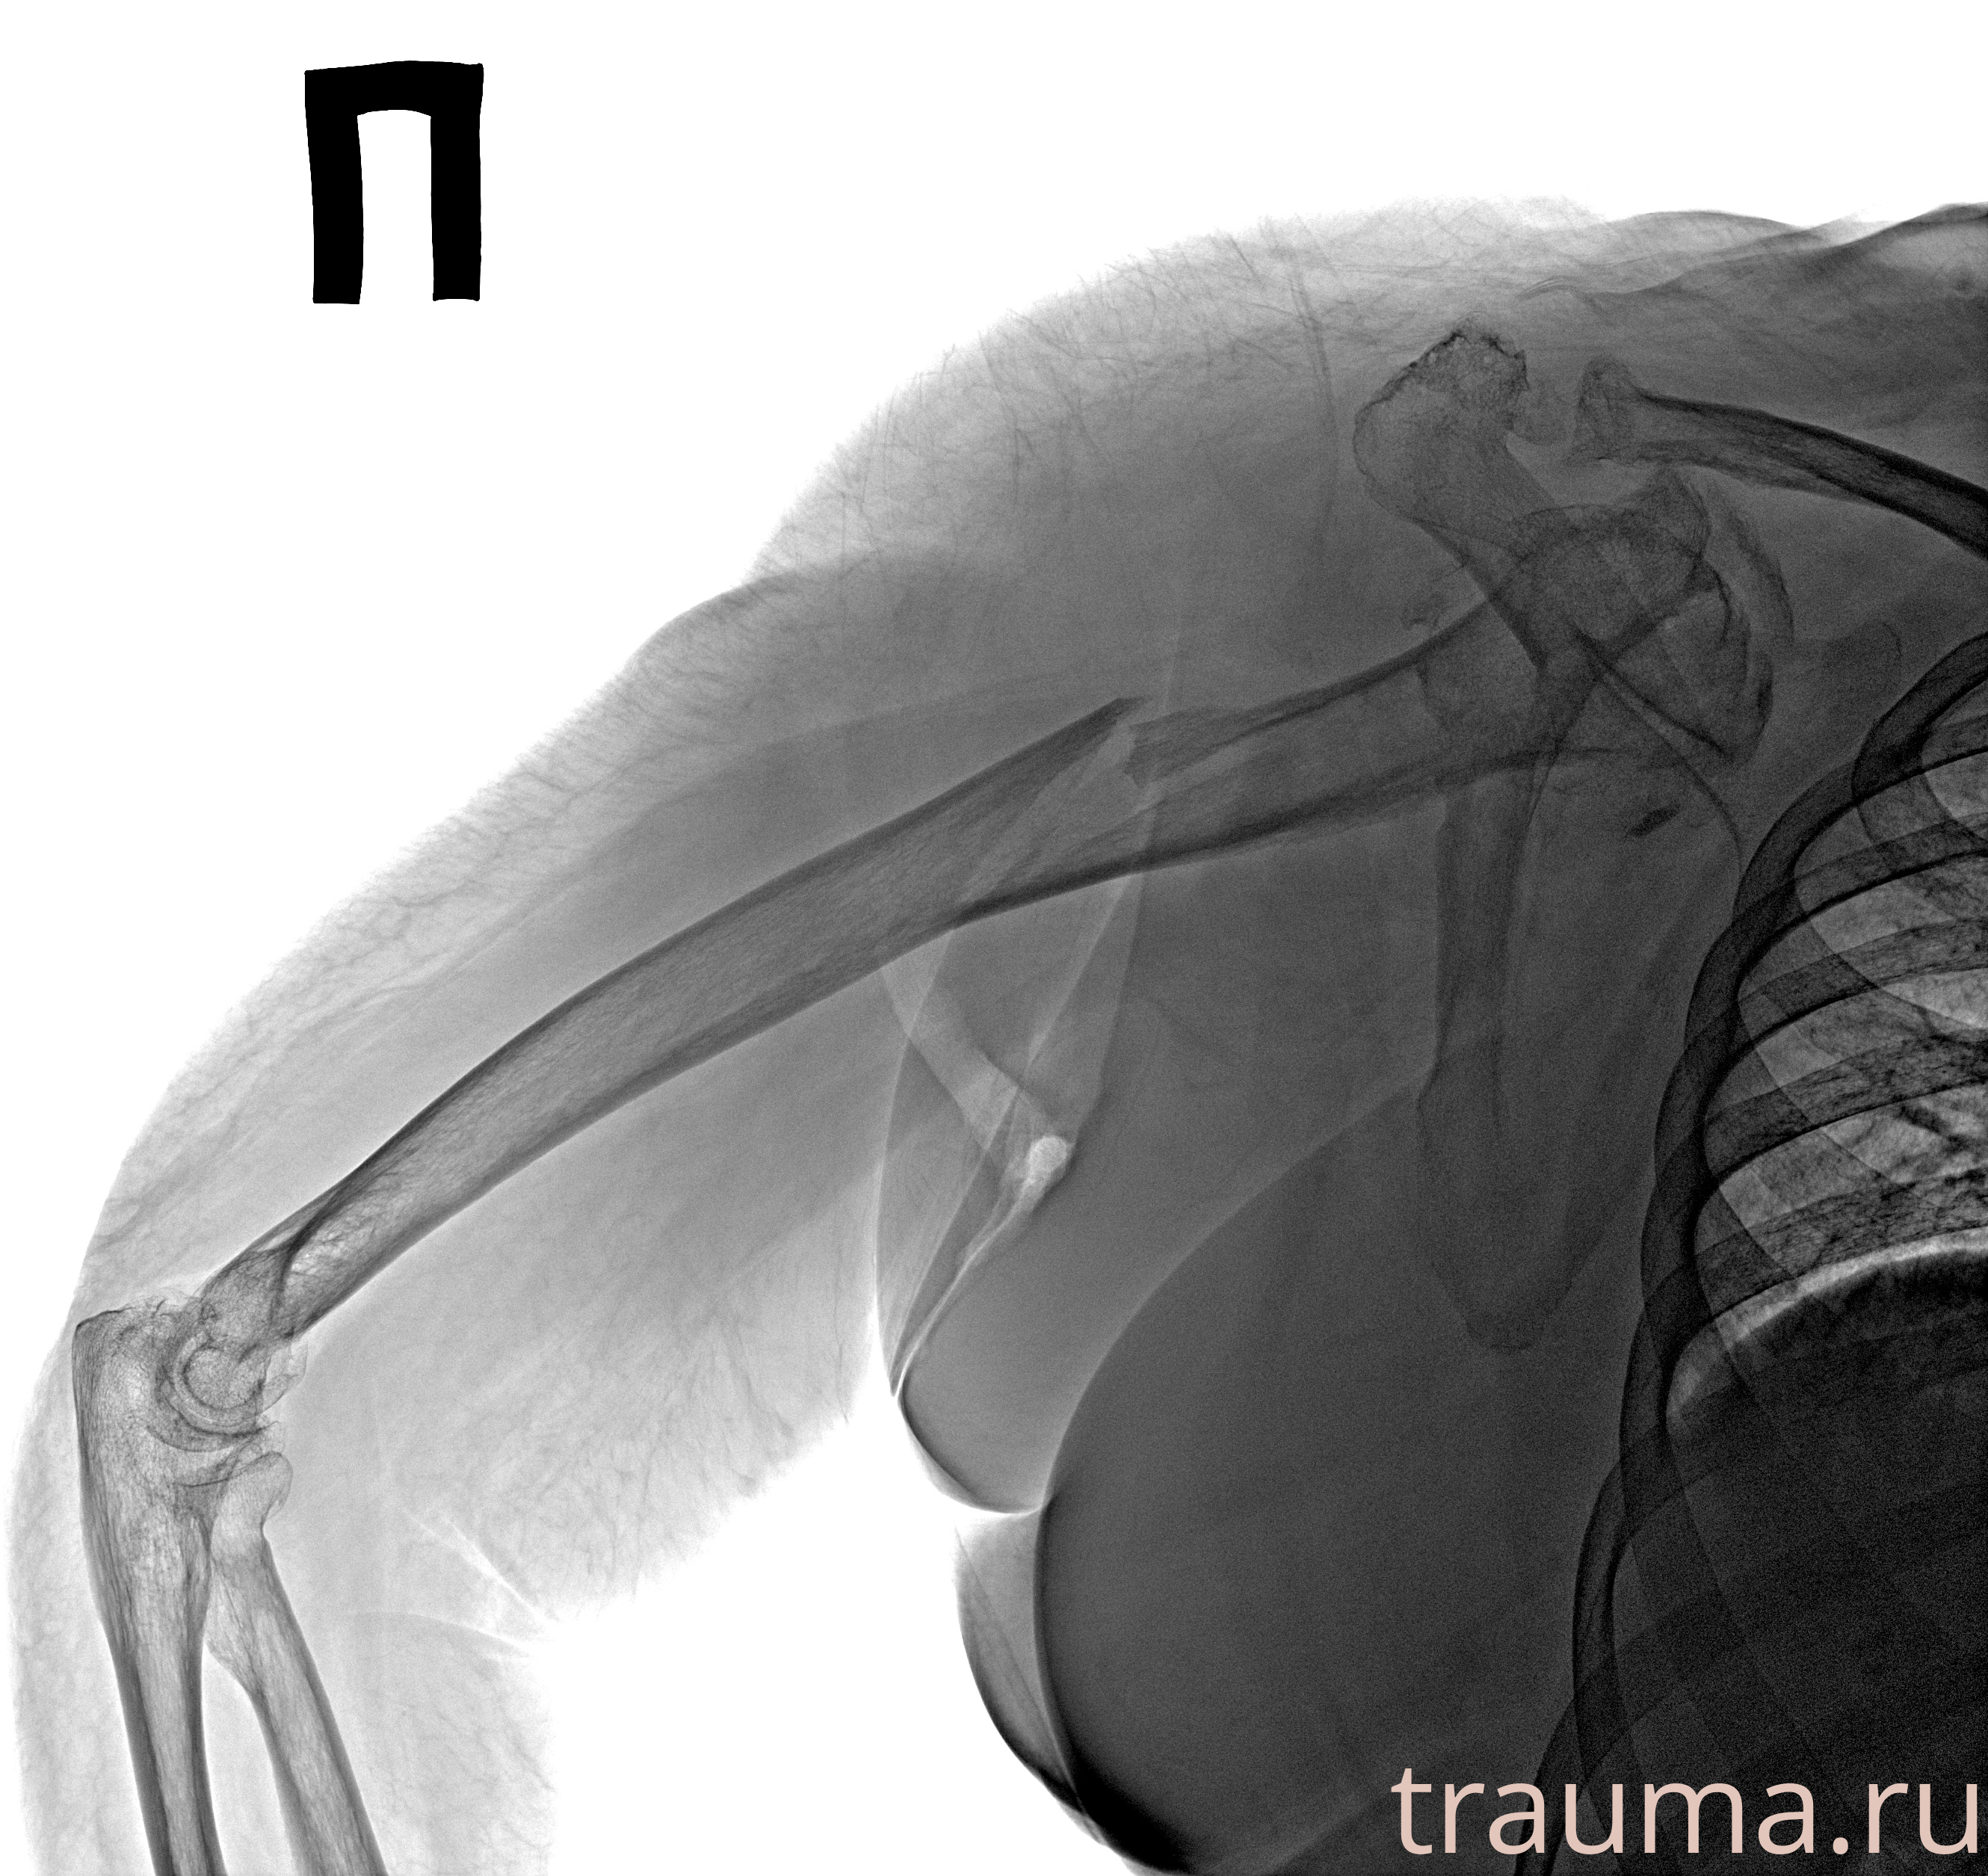

Рентгенограммы

Рентген на дому: по вашему адресу приезжает врач-рентгенолог, травматолог-ортопед с мобильным рентгеновским аппаратом, проводит диагностику травмы или заболевания, делает необходимые рентгенограммы, дает рекомендации по дальнейшему лечению. Получить качественные снимки в домашних условиях возможно благодаря уникальной методике, разработанной МосРентген Центром для института  Склифосовского